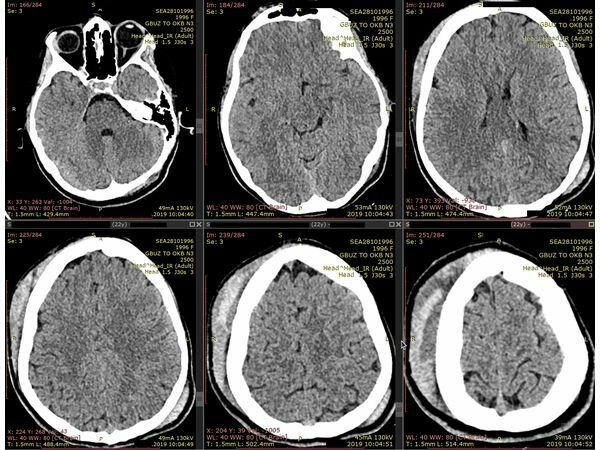

Ожидаемый объем глубокого церебрального внутричерепного кровоизлияния с МНО > 3,0, полученный через 2 часа после начала заболевания, составляет 15,33 мл × 2,64 = 40,47 мл. Влияние МНО в этом случае показано на рисунке, где показаны кровоизлияния объемом 15 и 40 мл.

Открыть в отдельном окне

мл (А) и 40 мл (В) глубоких мозговых внутримозговых кровоизлияний (ВМК). Это приблизительно соответствует разнице между ICH с международным нормализованным отношением (INR) <1,2 и ICH с INR >3,0, как видно из многопараметрической обобщенной линейной модели.